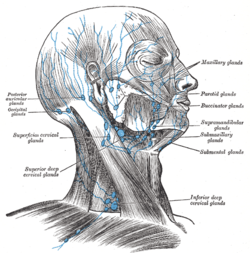

Superficial lymph glands and lymphatic vessels of head and neck.

The lymphatics of the face.